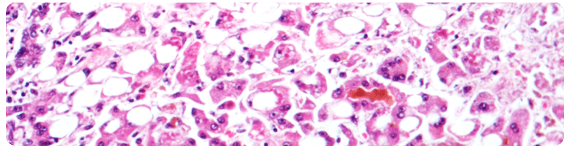

Varias citocinas proinflamatorias se han detectado en pacientes de AH. En los casos no complicados, la histología de AH está caracterizada por infiltración neutrofílica (marcador de hepatitis inducida por alcohol), degeneración ‘en balón’ de hepatocitos, necrosis manchada y fibrosis en el espacio perivenular y perisinusoidal de Disse, así como inclusión hialina de Mallory.